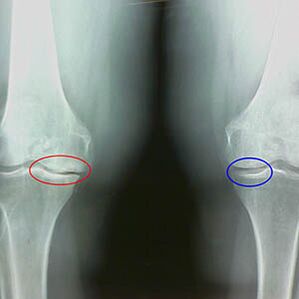

Features -Early X -Rays Second Stage of Knee Arthrosis:

- Sharp edges of tubercles between the tibia, where the cross -shaped ligaments are attached;

- narrowing the joint gap next to the medial side;

- Sharp edges of the bone - the bone back on the medial side, less frequently on the side - depending on the development of valgus or variable joint deformation.

For the second stage in LarsenThe joint narrowing of the gap with more than 50% is a feature, but this can only be checked in dynamic or comparison with joints that are not like.

Radiography shows the presence of osteophytes, a change in the space between the femoral and tibia bones, which indicates the loss of cartilage in the knee.Occasionally x -Ray knee joints show important signs of cartilage, but patients do not experience significant pain.On the other hand, the first stage arthrosis can interfere with the knee function, because the cause of pain is hypotonic muscles.